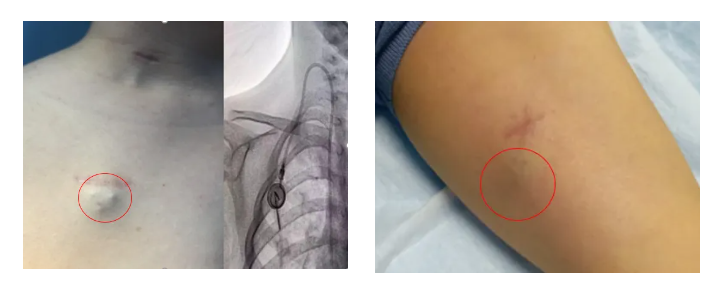

輸液港,即完全植入式輸液港(PORT),是一種可完全植入皮下并長期留存體內(nèi)的輸液裝置,主要由注射座(又稱港體)和硅膠導(dǎo)管兩部分組成。注射座被埋植于胸部皮下,導(dǎo)管則連接到上腔靜脈,形成一個(gè)閉合的靜脈輸液系統(tǒng)。其常見類型有手臂輸液港與胸壁輸液港。

提高生活質(zhì)量:輸液港埋植體內(nèi),外觀無外漏導(dǎo)管,患者可自由活動(dòng)。